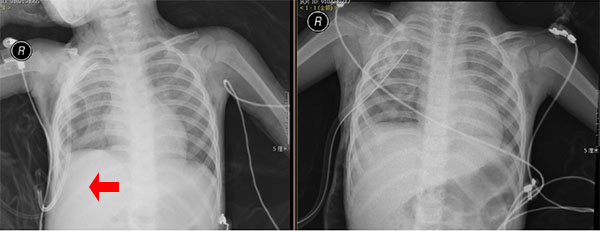

患儿手术前后的胸片对比(箭头所示为右上肺囊肿)

1岁11月幼儿右上肺巨大肺大泡并气胸